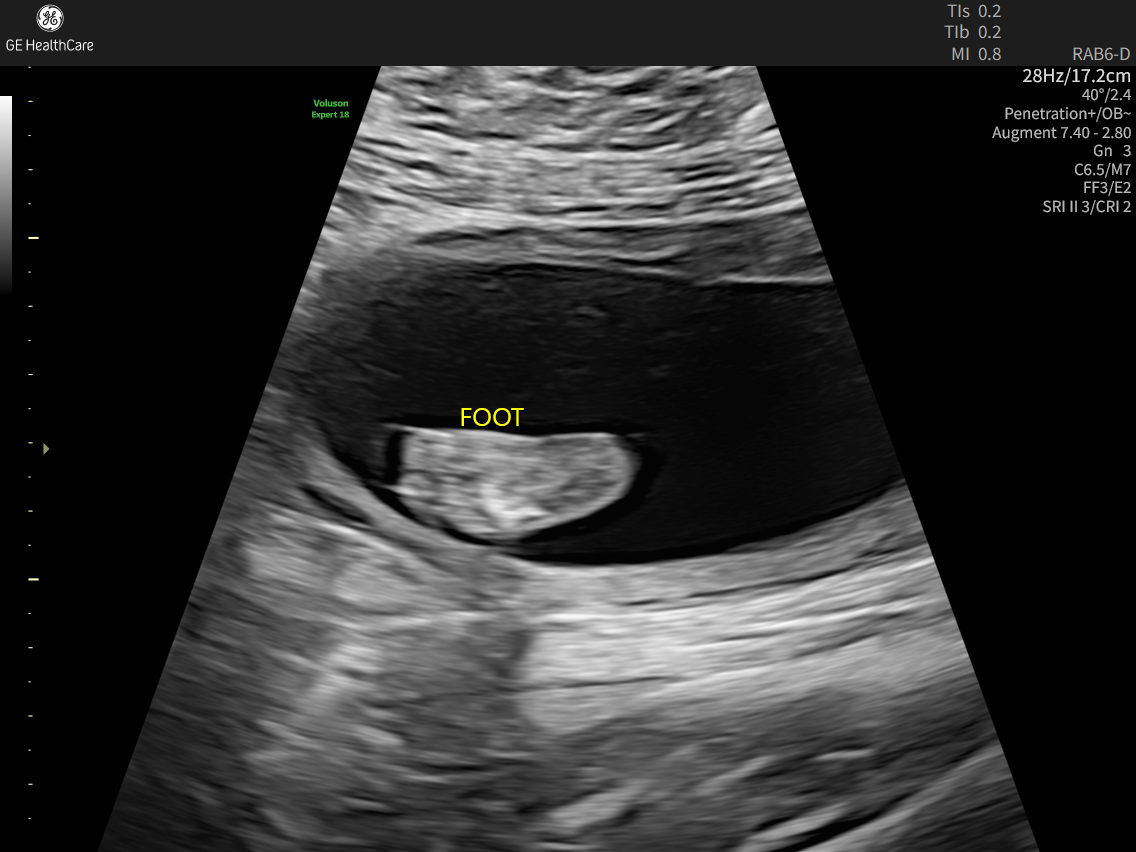

Me and my husband found out we were pregnant on November 2nd. We had an appointment with a high-risk doctor on December 22nd where a possible abdominal issue was found. We then went to our anatomy scan on February 2nd, and the abdominal issue they found at the previous appointment was worse than they originally anticipated. Our little girl was diagnosed with something called Limb-Body Wall Complex(LBWC). It basically means all of her internal organs are outside of her body, including part of her heart. It also can cause spinal issues, and her spine has a lot of curving that is not good. She’s basically twisted and curled up and “stuck” to the placenta wall to where she can’t really grow, and she’s measuring really small. It’s a fatal diagnosis and extremely rare. We have been going to weekly ultrasounds since for a weekly heartbeat check. Whenever we go in and there’s no heartbeat, we will go to labor and delivery and deliver her, unfortunately stillborn. There’s no known cause of this, nothing we did wrong, just a very sad and unfortunate circumstance. Any money donated will go to any hospital bills, time taken off work, a memorial service or cremation(whichever route we decide to go), Please keep us in your prayers over the next few weeks/months as we navigate this unimaginable and very tough time.❤️